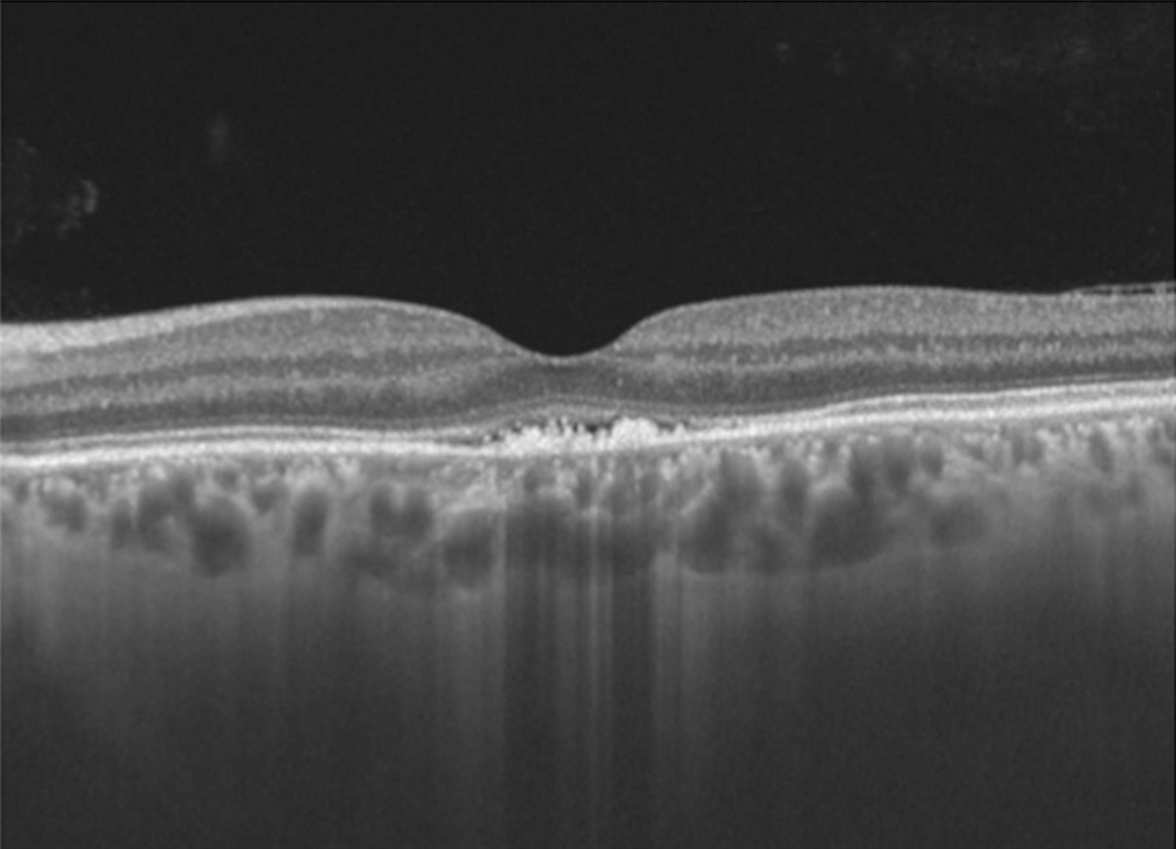

BONUS: 27-year-old woman presents following flu-like illness. Vision is 20/400. Fundus and OCT findings are shown below. Diagnosis? Prognosis?

BONUS: Acute idiopathic maculopathy.

-Vision loss + oftentimes a viral prodrome

-Turbid yellow-gray SRF with pigmentary changes

-OCT with hyperreflective debris in subretinal space +/- SRF.

- Prognosis is good so long as RPE not significantly damaged